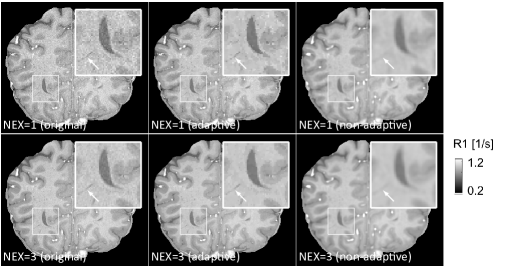

The results for each of the above mentioned algorithms can be found in Figures 3 and 4. We use the MRF reconstruction as initialization for the L-M algorithm, and compare that with the result of the BLIP algorithm when using a relatively refined dictionary. The advantage of integrated-physics approaches is evident by checking the reconstructions in Figure 3 as well as quantitatively by looking at the error maps in Figure 4. In this example, we have used a time series of the 1/8 Cartesian-subsampled k-space data (Fourier coefficients of magnetizations) of length 40. In the original MRF algorithm (typically requiring a large time series of k-space data), this test setting is far from yielding a reasonable result, while BLIP has improved a little by enforcing the projection to the Bloch manifold. But still one observes deficiencies. The method with integrated physics, however, appears to be efficient and it returns the best results among the three methods.

In [178] a line-search strategy is proposed to find the step size-parameter that has to be adjusted in dependence of the unknown Lipschitz constant of in order to guarantee a sufficient descent of the objective in each step of the algorithm. The overall method alternates between the three optimization steps and is shown to converge against a limiting-stationary point. Prototypical numerical results from [178] are depicted in Figure 9, where the dictionary learning approach is compared against the pure Levenberg-Marquardt method from Section (2.2) and the BLIP method in [52]. Here the number of image frames was chosen to be and the under-sampling factor is 16. Moreover small complex noise was added to the under sampled Fourier data. The details can be found in [178] where also extensions of the methods are discussed.